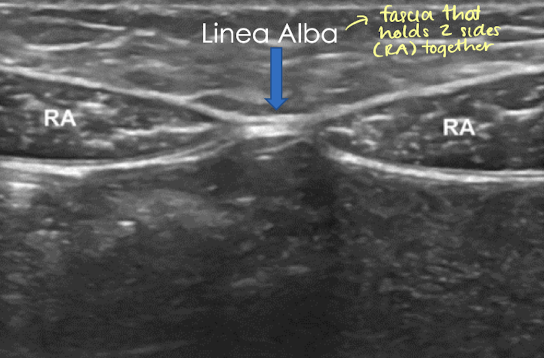

rectus abdominis

greater pelvis muscle

paired muscles that run vertically on side of anterior abdominal wall (6-pack)

extends from symphysis pubic to costal cartilages of ribs

controls pelvis tilt and curvature of lower spine

SONO: rectus abdominis

hypoechoic with echogenic striations in LONG

right and left rectus abdominis muscles join linea alba (echogenic) which courses along abdominal midline